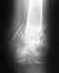

Плохо срастается перелом лучевой кисти.

26 ноября 2003г. в результате падения произошёл перелом лучевой кисти правой руки со смещением. Была проведена операция с использованием металлической спицы. В течении двух месяцев рука была в гипсе, сначала до плеча, затем до локтя, позднее гипс заменили на жёсткую конструкцию,которую можно снимать. В результате последнего ренгена в конце февраля 2004г. выяснилось, что перелом плохо срастается. Врач, делавший операцию и консультировавшийся с другими специалистами, не может объяснить почему это происходит и снова предлагает загипсовать руку. Меня очень тревожит не слишком ли долго рука будет находится без движений и не пострадают ли при этом непоправимо мышечные ткани.Буду очень благодарна за косультацию.